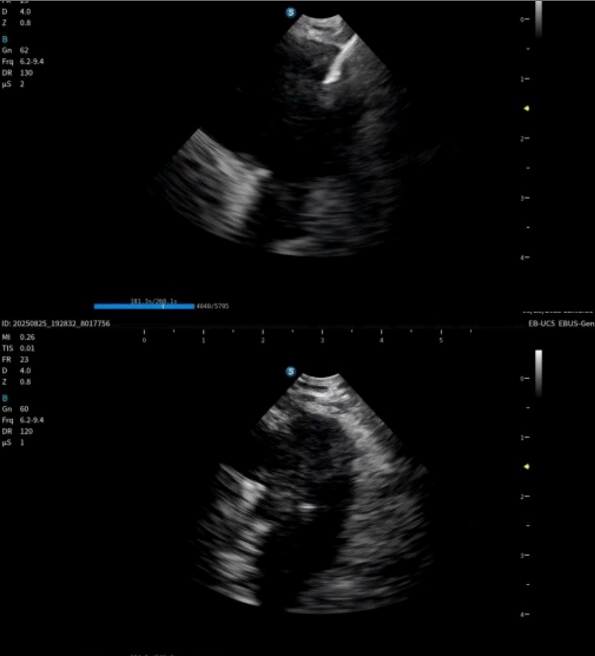

9月1日,开立医疗隆重推出一体式超声内镜系统和分体式超声内镜系统全系列产品,并且同时获得欧盟CE(MDR)认证,成为国产首台进入欧盟市场的超声电子支气管内窥镜系统,实现国产高端呼吸内镜领域重大突破,为中国创新医疗器械走向全球市场再添里程碑。

本次获证标志着开立医疗实现国内首家在该领域做到产品系列最齐,功能最完备的超声电子支气管内窥镜系统:超声电子支气管内窥镜+高清电子支气管镜+超声微探头+一体式超声内镜主机+分体式超声内镜主机,可满足不同呼吸诊疗术式临床应用需求。

作为在呼吸诊疗领域的重磅产品,本次在产品创新设计上和工艺技术上取得了重大突破,显著提升了光学图像和超声图像的质量,同时镜体保持了良好的操作性,在钳镜比和视野角综合参数可达到全球同类产品最佳性能。目前在临床应用表现突出,取得了专家的认可和好评。

超声电子支气管内窥镜凭借其"微创、精准、安全"的特点,已成为呼吸介入领域的核心技术之一。开立医疗全系列产品全面上市可为肺部肿瘤、纵隔病变提供管内清晰光学影像,管外高清声学断层组织及血流影像,提供精准可视化介入操作,为疾病的诊断提供更精准、更安全、更高效的一体化诊疗解决方案。